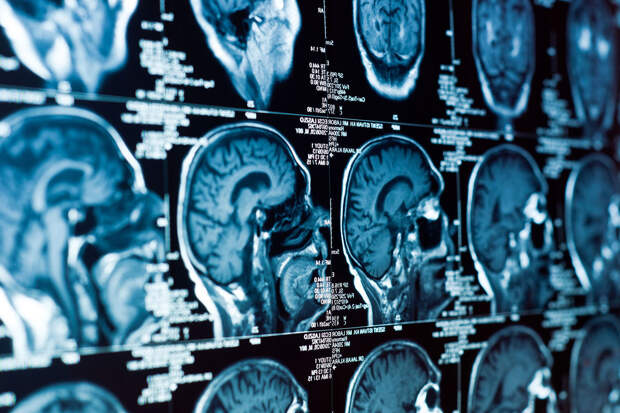

Об этом "Газете.Ru" рассказали в компании.Компьютерная томография (КТ) применяется в медицине для диагностики болезней внутренних органов без проведения операции. Томограф сначала получает рентгеновские снимки органа под разными углами, а затем специальными алгоритмами преобразует их в цифровое 3D-изображение. Сейчас при съемке используется единый протокол — число снимков не зависит от индивидуальных особенностей человека, что может приводить к излишней радиационной нагрузке. Например, при стандартной процедуре КТ легких требуется снять около 10000 рентгенограмм.

Исследователи разработали нейросеть, отслеживающую качество анализируемого изображения непосредственно во время сбора проекций. Изображение реконструируется по неполным данным. После получения каждой частичной реконструкции ИИ анализирует качество 3D-изображения, и, если информации для постановки диагноза достаточно, процедура завершается досрочно.